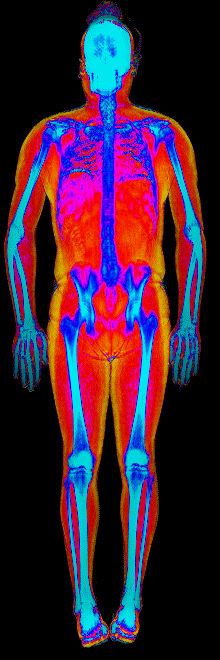

A DEXA scan passes two low-dose X-ray beams through your entire body, head to toe. Different tissues absorb different amounts of energy: bone absorbs the most, muscle and lean tissue less, and fat the least. The scanner reads how much energy made it through every pixel and assigns each one to a tissue type.

The colorful image at the top of every BodyStats DEXA report is literally that map. Bone shows up in cyan and white. Lean tissue is red. Fat is yellow and orange. Your body-fat percentage isn’t an inference — it’s a count of how much of that image is yellow and orange, broken out region by region: left arm vs right, left leg vs right, trunk, android (belly), gynoid (hips). And visceral fat — the dangerous abdominal fat that bioimpedance can’t see at all — comes back as its own number in cm².

This page features real, anonymized DEXA scan images from BodyStats clients, organized by gender and body fat percentage in 5% increments. DEXA (Dual-Energy X-ray Absorptiometry) is the clinical gold standard for measuring body composition — far more accurate than scales, calipers, or visual estimates.

Each colorized scan shows the distribution of fat tissue (shown in warmer colors) and lean tissue (cooler colors) throughout the body. Compare your own DEXA scan to others in your range, or see what different body fat levels actually look like on a scan.

Male DEXA Scans by Body Fat %